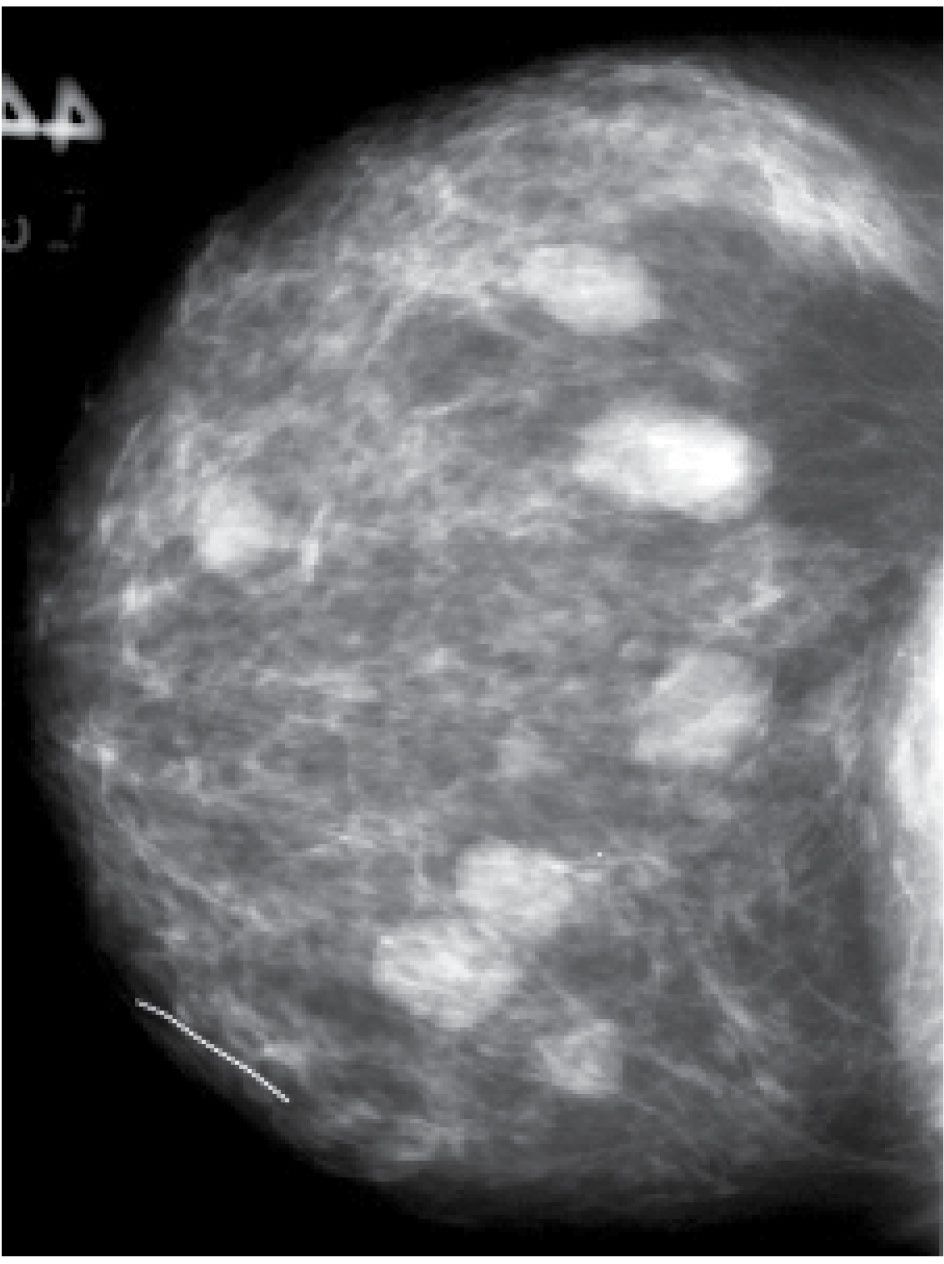

Фиброаденома молочной железы - доброкачественное образование, которое часто встречается у женщин. Оно может быть обнаружено при помощи различных методов диагностики, включая маммографию. Ниже представлены фотографии, помогающие понять, как выглядит данное заболевание.

Маммография и ее роль в диагностике фиброаденомы молочной железы

Маммография - это рентгенологическое исследование молочных желез. Оно позволяет выявить различные изменения в тканях, включая фиброаденому. На маммограммах можно увидеть структурные особенности опухоли и отследить ее динамику во времени.